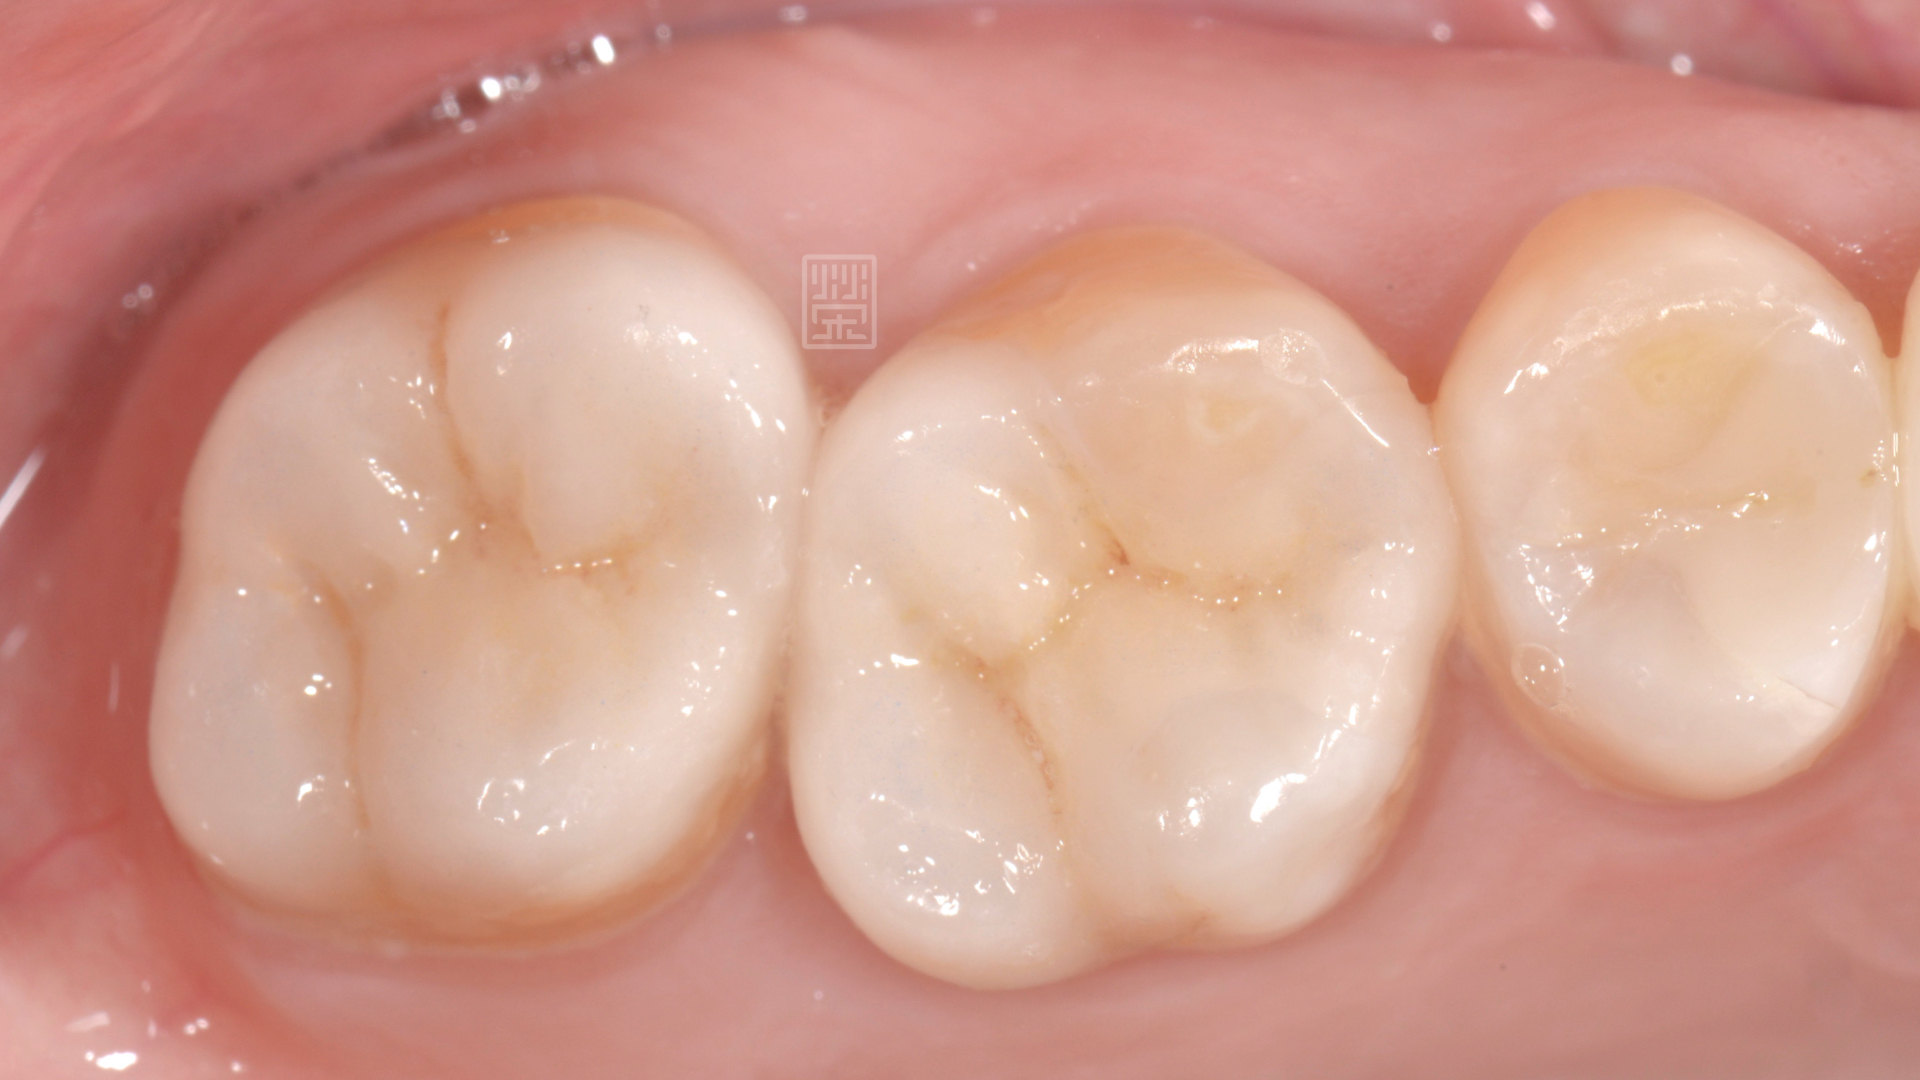

在清除蛀牙、舊的填補誤之後,利用全瓷黏著贋復物,恢復型態與功能,讓陳小姐能夠自在的享用美食。

全瓷嵌體完成